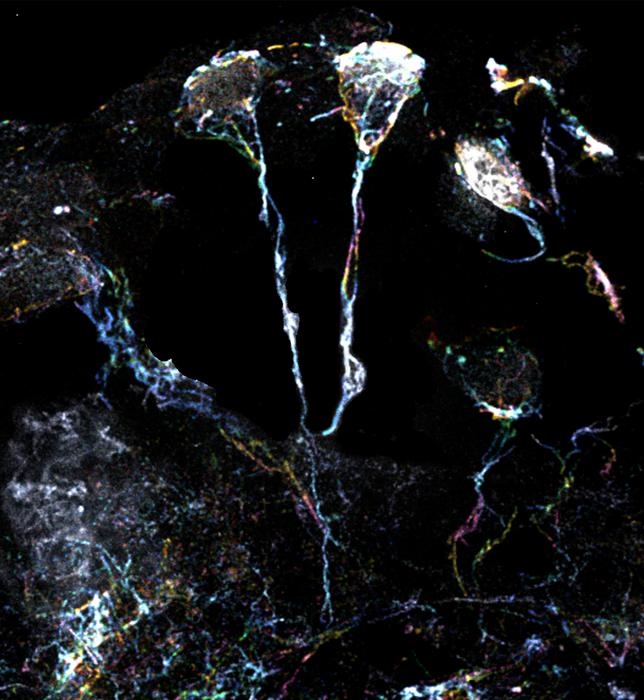

在果蝇大脑中,休眠的神经干细胞具有富含肌动蛋白丝的突起。 图片来源:杜克-新加坡国立大学医学院

为了研究这种激活,研究团队将目光转向了果蝇。与哺乳动物类似,果蝇的神经干细胞在被唤醒之前一直处于休眠状态。团队使用放大倍数为10倍的超分辨率显微镜,检查了果蝇休眠神经干细胞的标志性微小纤维结构。这些细微结构的直径约为1.5微米,一种特定类型的Formin蛋白可激活这些细丝并使其组装。